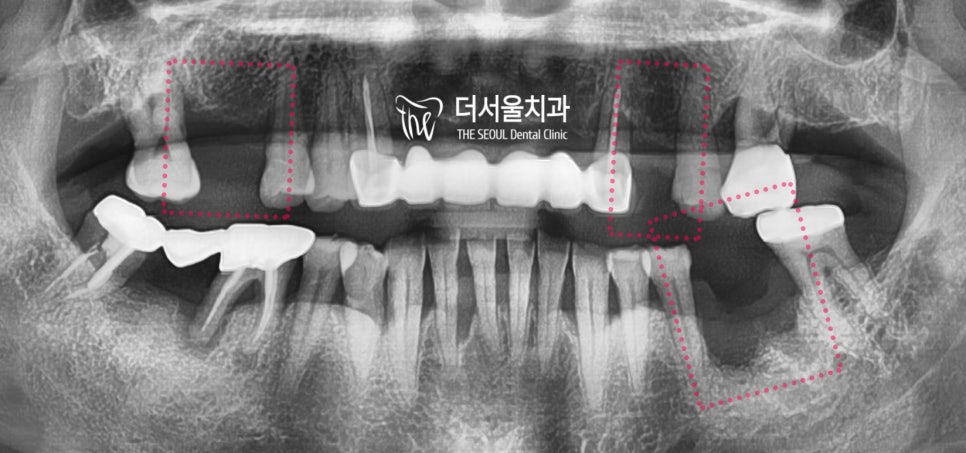

『c.c : 어금니가 없어요.』

상악에는 2곳에서 치아의 결손이 관찰되며

전체 엑스레이로 보게 되면 3곳에서

치아 결손이 관찰 됩니다.

지금 당장 식사를 하는것은 문제가 되지 않지만

이 상태를 그대로 유지를 하게 된다면

추후에는 더 큰 문제가 일어나기 쉬운 상태입니다.

치아 결손 부위에 따라서, 주위에 있는 치아들이

그 빈 틈을 메꾸려 이동을 하게 될 것이고

그에 따라서 결국 교합관계들이 무너지면서

식사를 하는것이 어렵게 되는 상황이

찾아올 수 있게 되는겁니다.